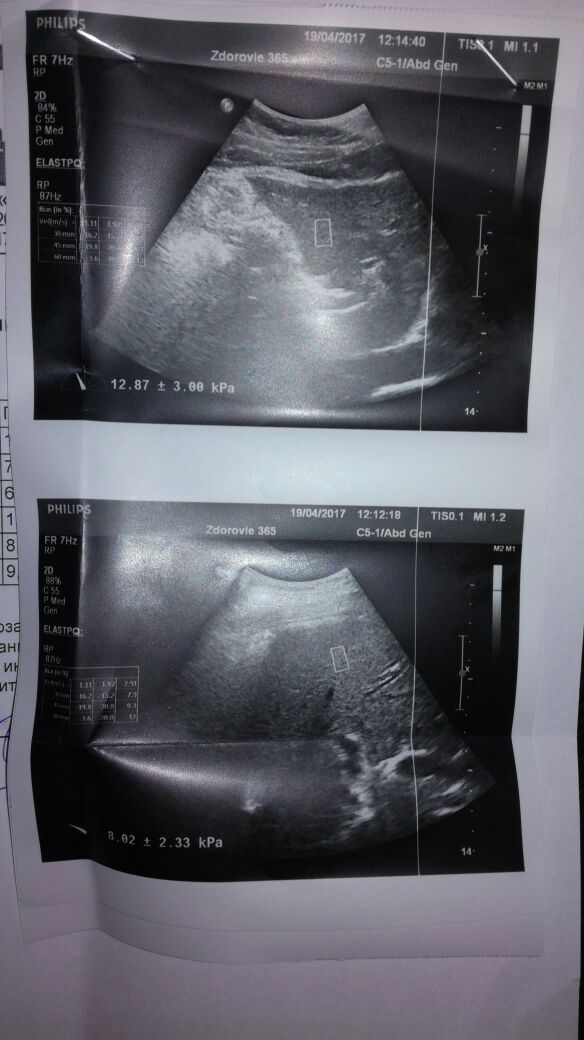

23.03.17 21,3кПа 03.04.17 14,4кПа 19.04.17 8,3кПа

Узи заключение

И фоток еще порядком везде прикреплено

Печенюшка)))